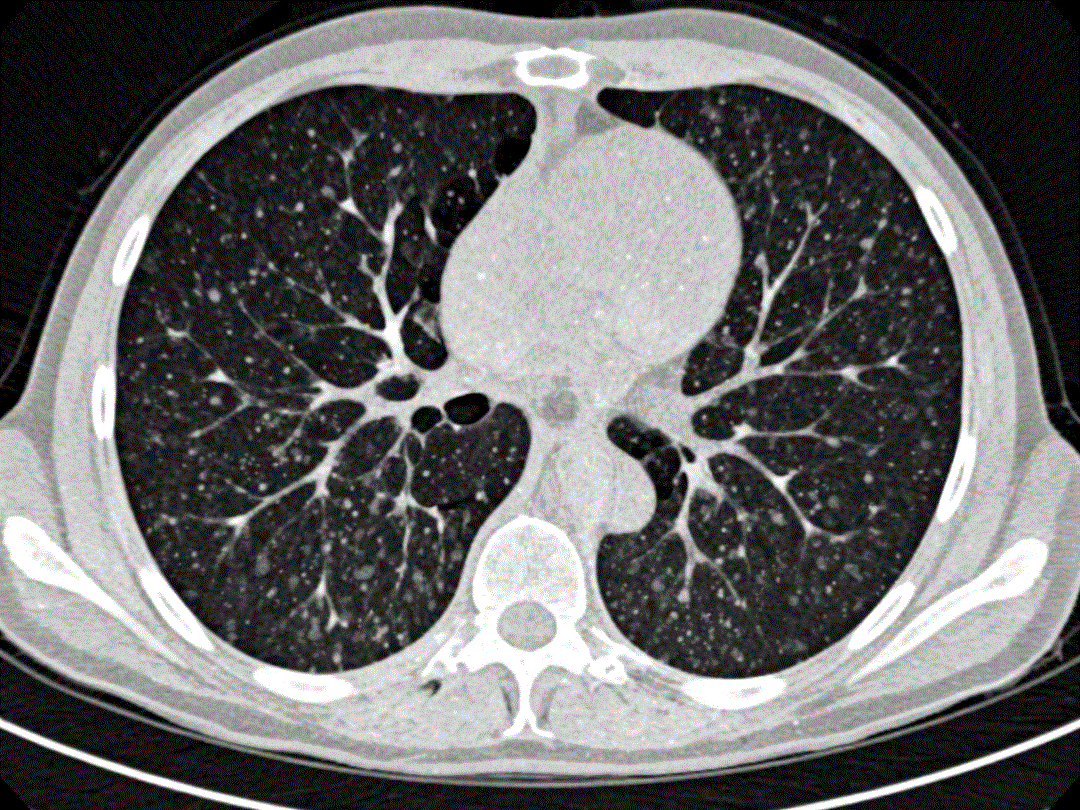

而如今筛查的“金标准”——低剂量螺旋CT,则像是给肺部做了一次精细的“切片扫描”。它能生成数百张清晰的横断面图像,将肺里的情况一览无余。即便是小至几毫米的“磨玻璃结节”(一种早期肺癌的常见表现),也难逃它的法眼。